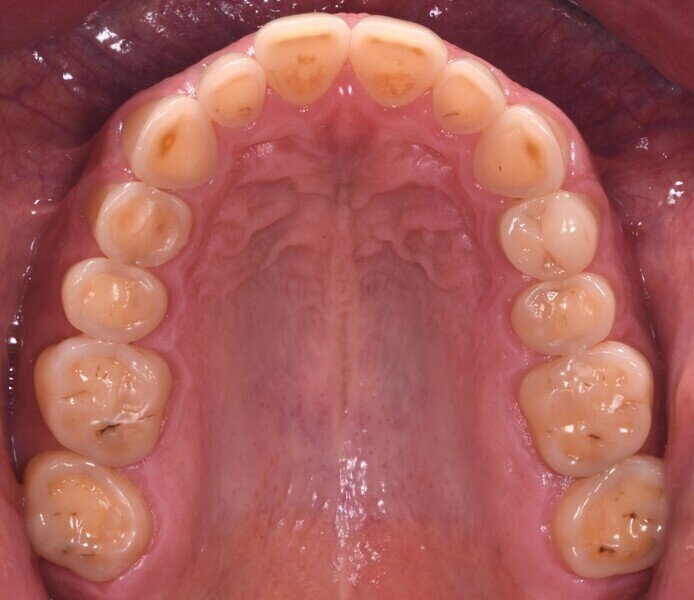

Do naší ordinace přišel 42letý muž, který doufal ve vylepšení svého úsměvu. Byl si vědom opotřebení chrupu v předním úseku a také některých zadních zubů. Tato situace vedla k obnažení značné oblasti dentinu, což způsobilo vysokou citlivost a negativně ovlivnilo estetiku jeho úsměvu (obr. 1). Dále se u něj projevilo určité stěsnání a vztah stoliček III. třídy, což mělo za následek určitou modifikaci okluze, tendenci ke vztahu řezáků III. třídy a skus hrana na hranu (obr. 2).